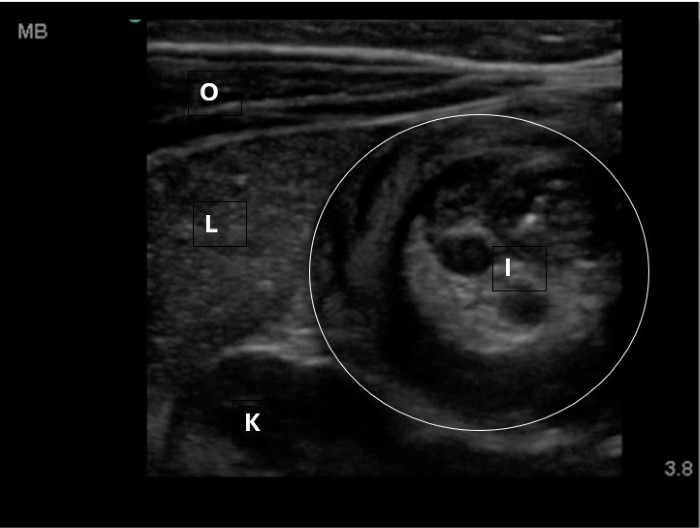

The linear probe is placed in the RLQ in the transverse position with indicator to the patient’s right. Identify the psoas muscle and iliac vessels lying medial. Once these structures are visualized, slide lateral and look superficially to identify the cecum. (Figures 1a,1b 1) Use graded compression-progressive increase and decrease of pressure to move any gas out of view. Keeping the lateral edge of the abdominal cavity in view (Figure 2), the ultrasound probe should slide cranial in traverse plane, visualizing the ascending colon until the hepatic flexure.  In this location, the colon turns just medial to the liver with the kidney deep in the view. (Figure 3) This is the most common location to identify ileocolic intussusception. If no tissue mass is identified, the probe should be turned to the sagittal plane with indicator toward the head (to keep the colon visualized in the transverse view) and moved across the transverse colon continuing to use graded compression to look for a tissue mass consistent with intussusception. Once at the splenic flexure (Figure 4), the probe should be transitioned back to the transverse orientation to interrogate the descending colon.

The abnormal structure of intussusception is a rounded tissue mass in the transverse axis with a hyperechoic center and hypoechoic outer muscle layer (Figure 5) and in long axis appears as a “pseudokidney.” (Figure 6) Outer dark edge to edge should be at least 2cm.1-3 Smaller structures with similar appearance are likely ileo-ileal intussusception, which is usually psychologic and does not typically require intervention.

10-2024 Article7-3.jpgFigure 3. Hepatic flexure view in a patient with intussusception. Oblique abdominal muscles, liver, kidney visible. Intussusception will be medial to the liver and superficial to the kidney.